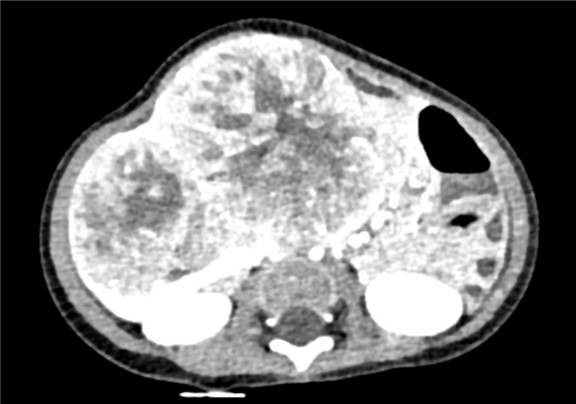

模拟手术操作,自动计算切除肿瘤体积。肝脏体积为345.8ml,肿瘤体积383.5ml,是肝脏体积的1.1倍,通过比对6-9月岁正常肝脏体积为257.75±51.05ml,通过术前模拟手术,精准判断切除后剩余肝脏体积能耐受,避免肝衰竭发生。

麻醉成功后,病人平卧位,常规碘伏消毒手术区皮肤,铺无菌巾、单。取右肋缘下切口,分层入腹,纱布垫护皮。 探查见:肝脏肿瘤巨大,于右肝Ⅳ、Ⅴ、Ⅵ、Ⅶ、Ⅷ交界处可触及直径12cm圆形肿块,质韧,未侵及肝被膜,决定行右半肝切除术。断肝右三角韧带,冠状韧带,肝结肠韧带,游离右半肝。沿肿瘤边缘约1cm,用CUSA进行干燥切除,依次钳夹、切断、结扎肝断面各结构,切除肿瘤及部分肝组织。断面渗血处分别缝扎止血,填塞止血敷料后,将创面对拢缝合。温蒸馏水1000ml冲洗腹腔,止血,于肝断面旁放置引流管1根于右侧腹穿孔引出。清点纱布器械无误,分层缝合腹壁切口。术中出血约20ml,术后血压稳定,术后病人安返病房。手术顺利,麻醉满意,解剖标本,见切除肝标本呈鱼肉样,断面有坏死,家属过目后送病理检查。病理示肝母细胞瘤。

术前三维重建:

重建图片